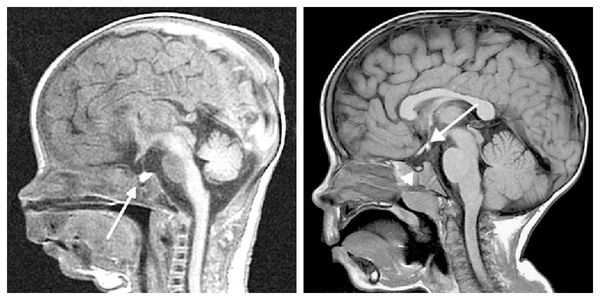

При необходимости проводится МРТ головного мозга и гипофиза с контрастированием[6]. Она позволяет исключить или подтвердить наличие объёмных образований области гипофиза и головного мозга.

Для выяснения формы нанизма необходимо исследование инсулиноподобного фактора роста (соматомедина-С), ТТГ, ЛГ, ФСГ, Т3, Т4, кортизола в плазме и моче, антител к тиреоглобулину, микросомальной фракции тироцитов и др. Для исключения опухолевого поражения проводится КТ (МРТ) головного мозга.

- Нейровизуализация. Чтобы обнаружить органические поражения гипоталамо-гипофизарной зоны, проводится рентгенография турецкого седла, МРТ или КТ головного мозга. При необходимости обследование дополняется церебральной ангиографией, электроэнцефалографией.

При необходимости проводится МРТ головного мозга и гипофиза с контрастированием [6] . Она позволяет исключить или подтвердить наличие объёмных образований области гипофиза и головного мозга.